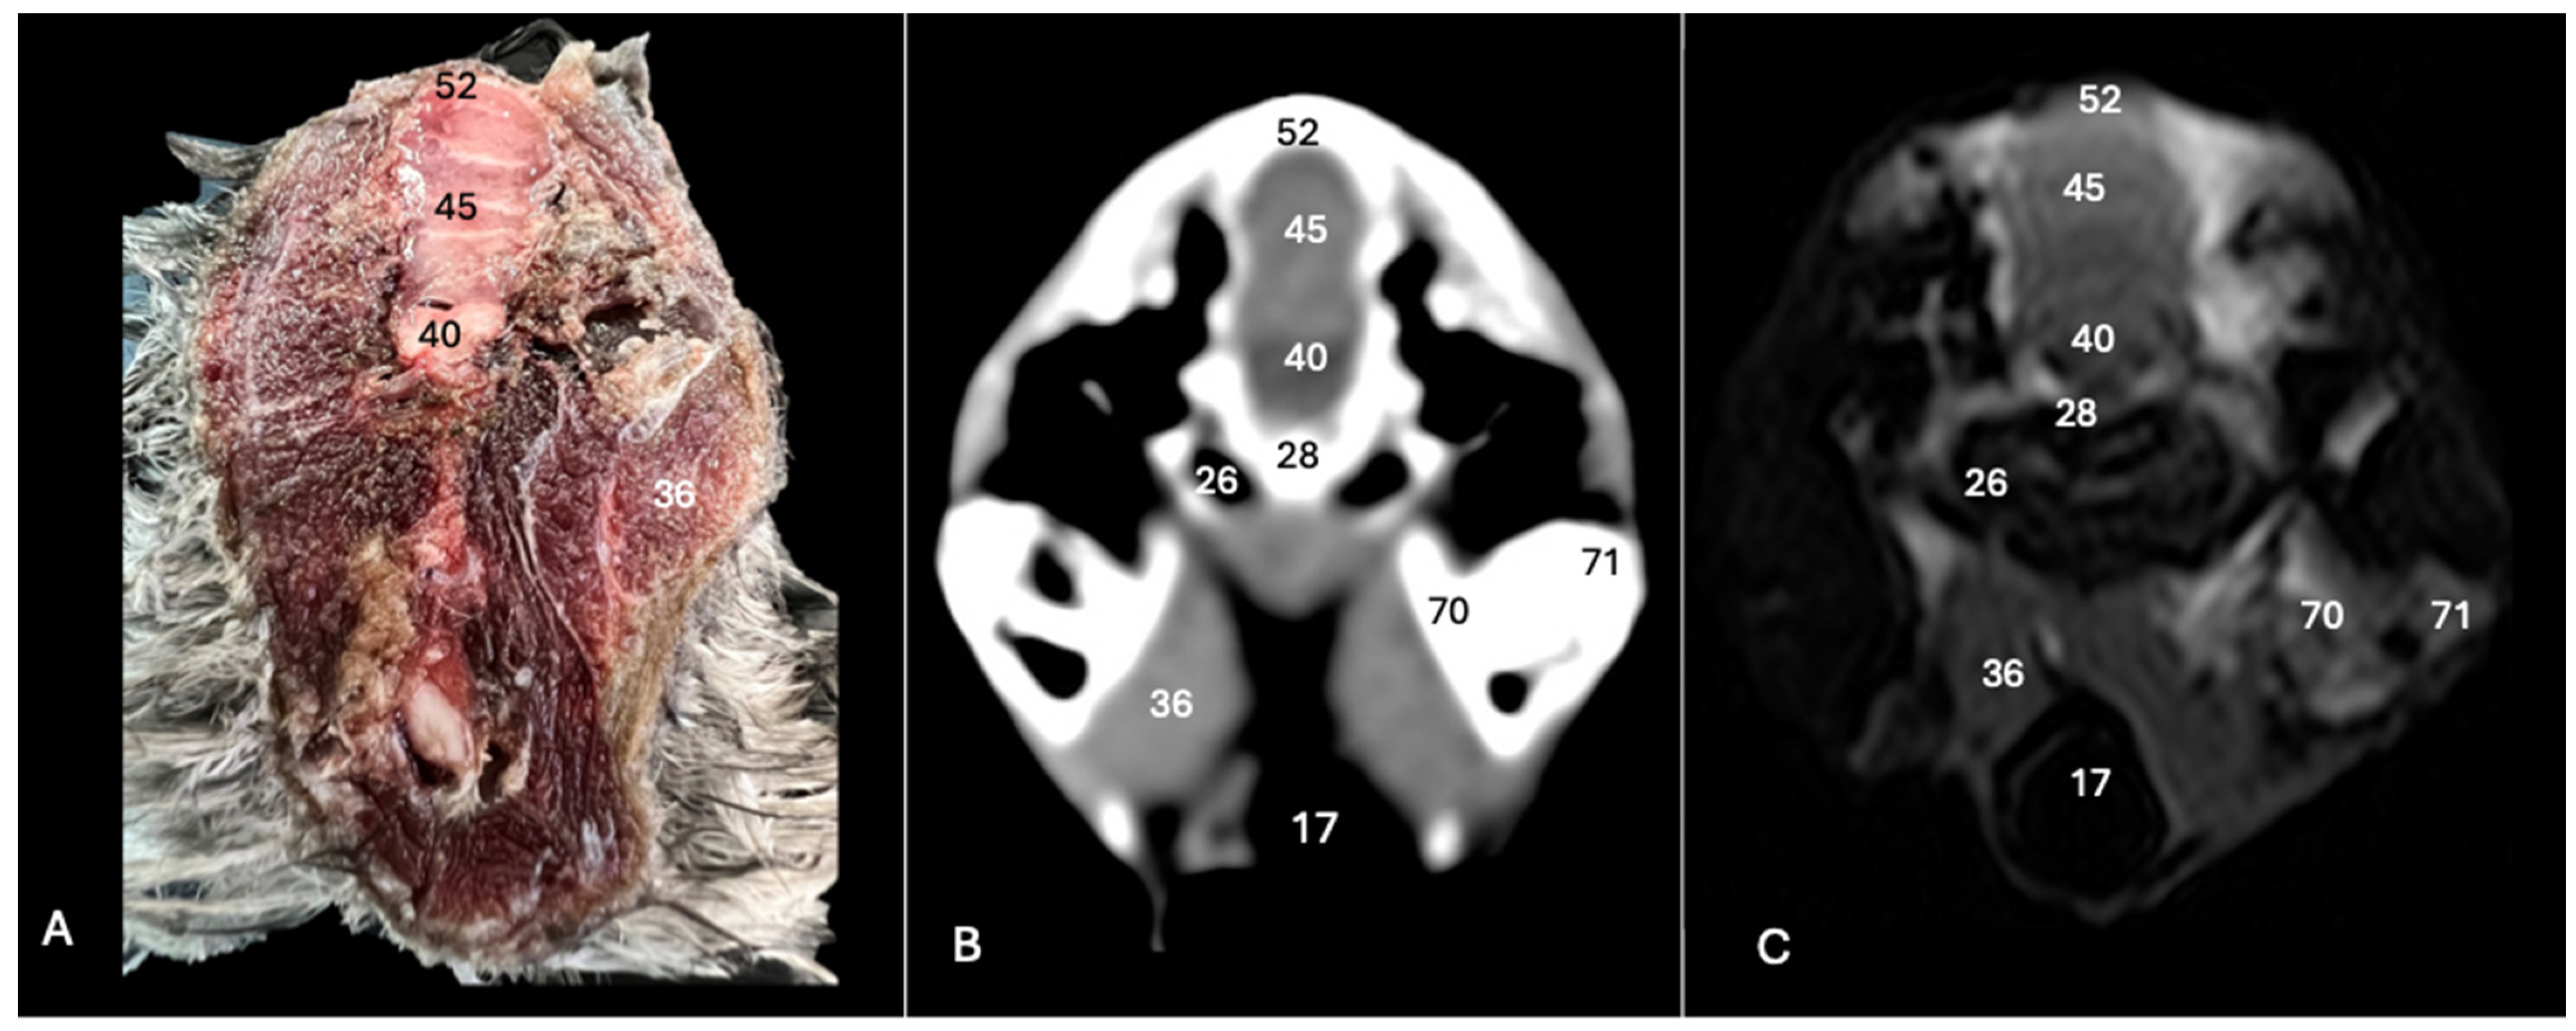

3. Result

3.1. Anatomical Sections

3.2. Computed Tomography (CT)

3.3. Magnetic Resonance Imaging (MRI)